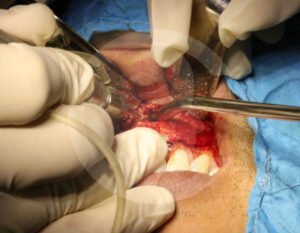

Un absceso es una acumulación de infección que puede causar dolor intenso e inflamación. Cuando el proceso infeccioso no mejora con tratamiento convencional, puede ser necesario realizar un drenaje o manejo quirúrgico.

Es una conexión entre la cavidad oral y el seno maxilar que puede ocurrir tras extracciones o infecciones. Su tratamiento busca cerrar adecuadamente la comunicación para evitar molestias e infecciones sinusales.

El tratamiento depende del origen y gravedad de la infección. Puede incluir medicamentos, drenaje quirúrgico o procedimientos específicos para eliminar el foco infeccioso y evitar complicaciones.

En casos de mayor complicación deberá ser ingresado a cuidados hospitalarios, y programar el procedimiento quirúrgico que corresponda